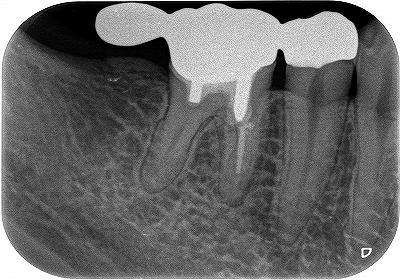

この部位は

以前、延長ブリッジが入っていた歯

遠心根に透過像が出てきており、歯茎からは膿が出てきていました。

日本の根管治療の約6割には問題があるというはあながち間違いではないと思います。

とりあえず根管治療をして治すことにしましたが、

近心根にはパフォーレーション 手付かずの遠心根には破折線が見られ、

患者さんにどうします!?遠心根はまず残せない、近心根は残すことが出来るがパフォーレーションの位置的に長く持たない可能性がある。

不思議なんですが、遠心根は根管治療していないにも関わらず折れてきている。

イメージ的に根管治療を行い中を削って歯を弱体化させている近心根が折れるならまだ分かるのですが・・・

患者さんと話し合い、近心根はヘミセクションをして残す 遠心根は抜歯

右下7の所には親知らずの移植と計画をしました。